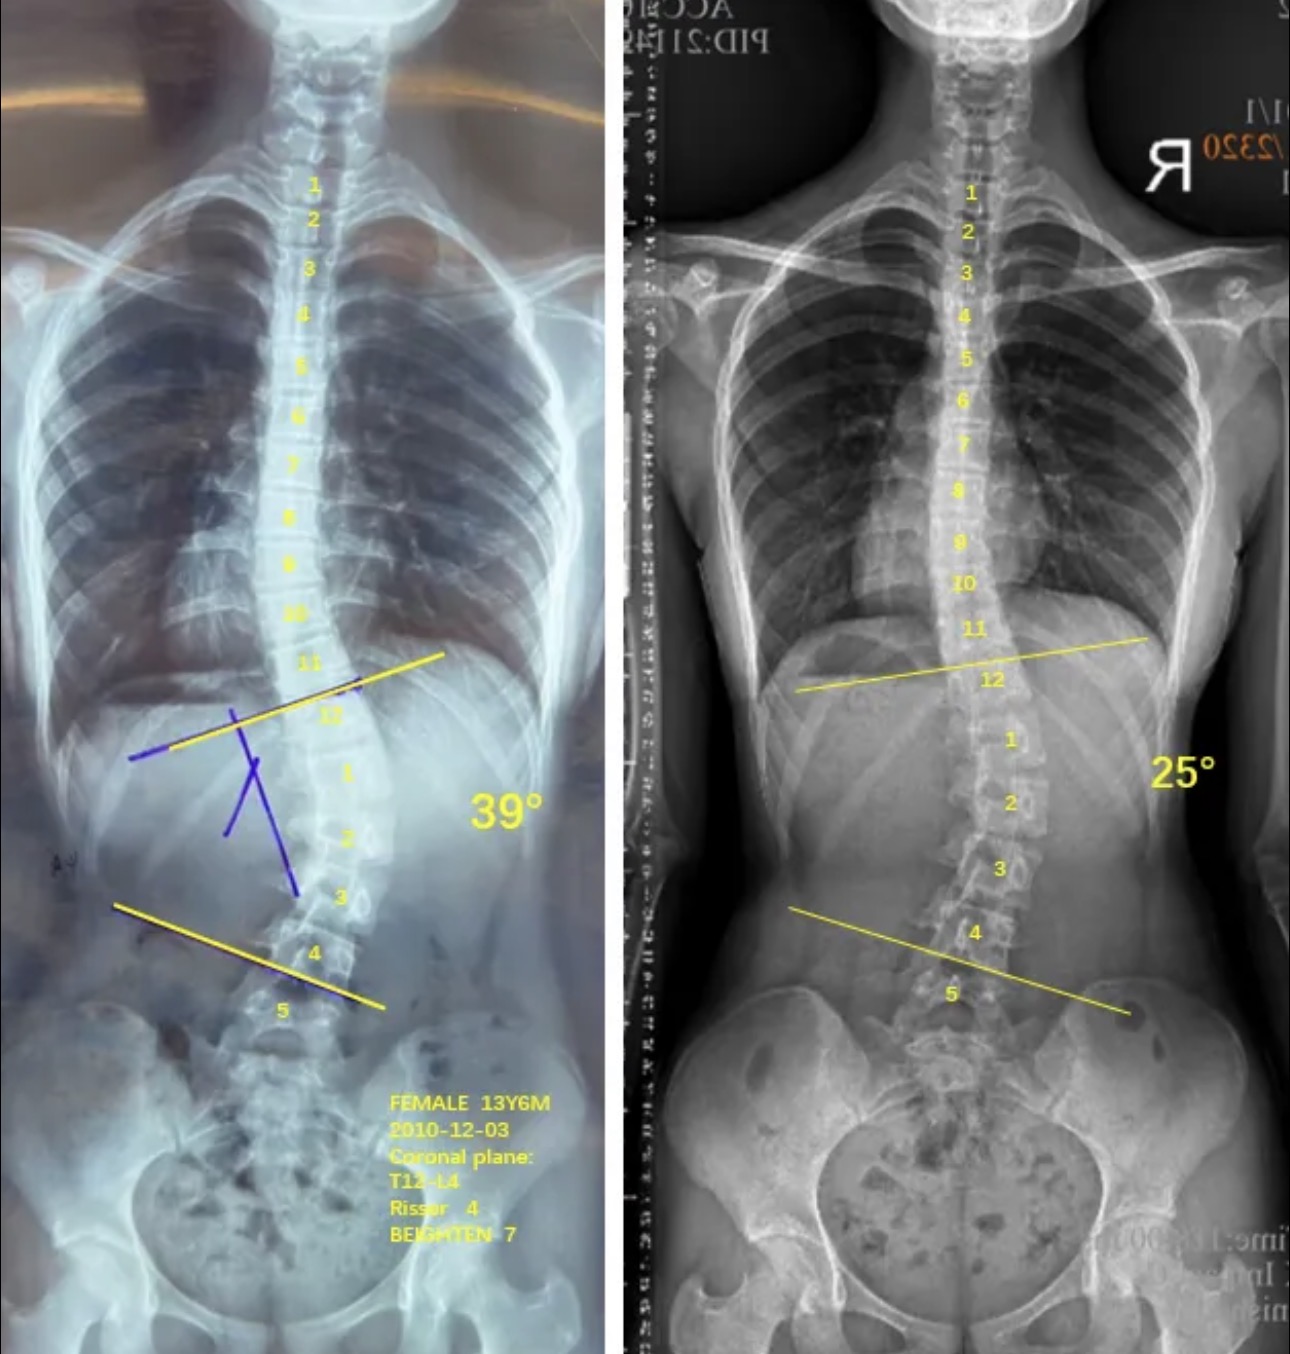

衷德脊柱,我们只关注侧弯保守治疗~

Zhongde Spine, bending no breaking ~